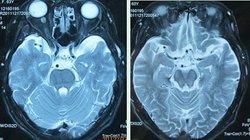

脫髓鞘疾病是一大類病因不相同,臨床表現各異,但有類同特徵的獲得性疾患,其特徵的病理變化是神經纖維的髓鞘脫失而神經細胞相對保持完整。髓鞘的作用是保護 神經元並使神經衝動在神經元上得到很快的傳遞,所以,髓鞘的脫失會使神經衝動的傳送受到影響。急性脫髓鞘性疾病的神經髓鞘可以再生,且速度較迅速,程度較完全,雖然再生的髓鞘較薄,但一般對功能恢復的影響不大。慢性脫髓鞘性神經病,由於反覆脫髓鞘與髓鞘的再生 許旺細胞明顯增殖,神經可變粗,並有軸突喪失,因此功能恢復不完全。脫髓鞘疾病中出現頭痛的機率不高,但脫髓鞘病人也有頭痛發作,歸納原因有兩方面:

這裡主要說說 多發性硬化病的主要症狀、體徵等。多發性硬化是因為自身免疫障礙而導致的 中樞神經系統的脫髓鞘性疾病。多在20-40歲之間發病,而在10歲以下和50歲以上發病者很少,起病可急可緩,表現為: